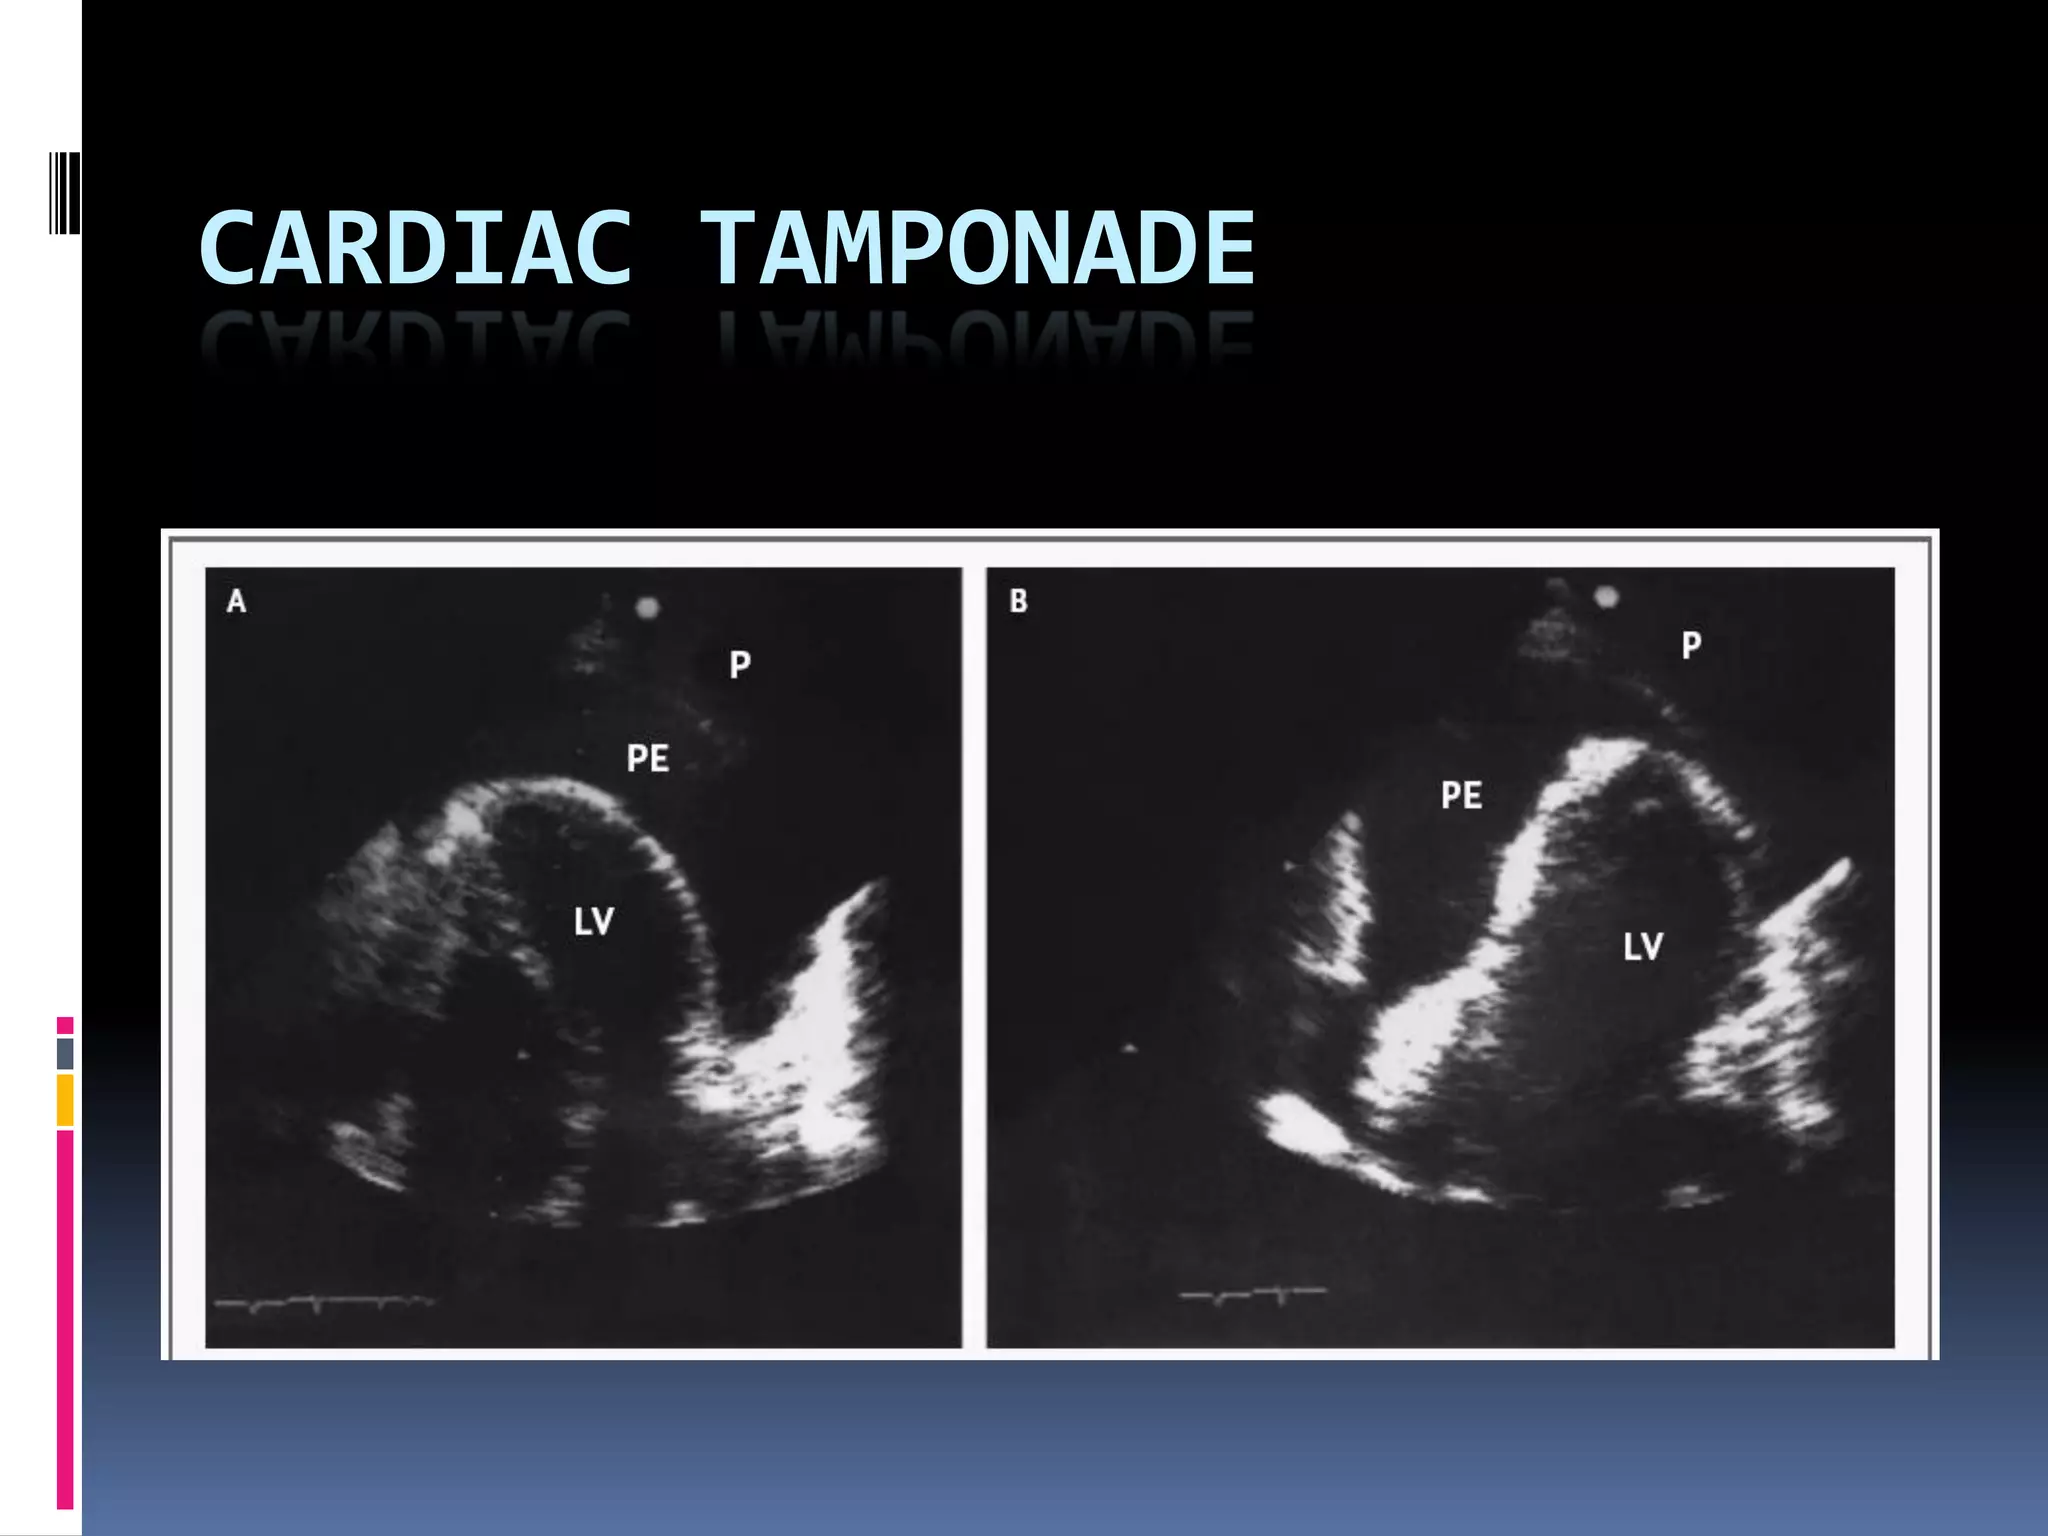

CARDIAC TAMPONADE

Pericardiocentesis

 If hemodynamic instability observed,

 Emergently performed underfluoroscopy or

echocardiographic guided

 With/without comfirmatory testing with

agitated saline injection

 Dramatical improvement is necessary

N Engl J Med 2003;349:684-90